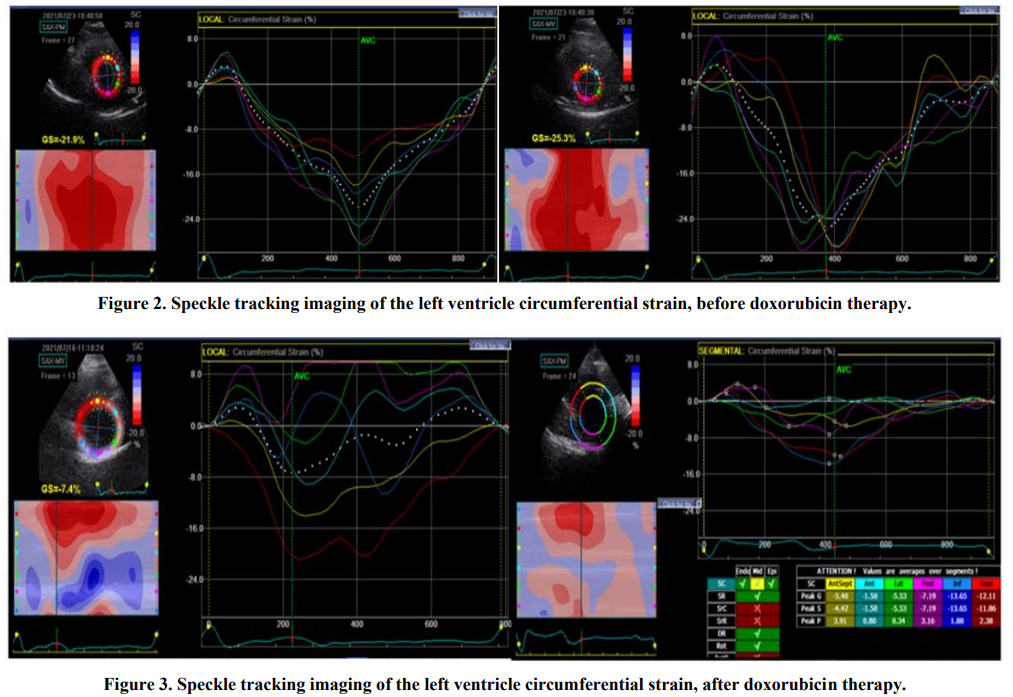

The Evolution of Imaging Markers in Cardiovascular Evaluation of Patients with Hematological Malignant Neoplasia

Flavia Deman, Minodora Andor, Ioana Ionita, Florina Caruntu, Valentina Buda, Mirela Cleopatra Tomescu

International Journal of Innovative Research in Medical Science·October 28, 2022